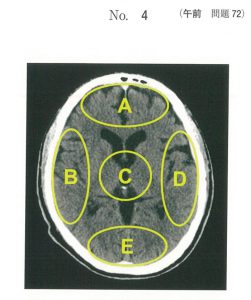

問題72

頭部CTを以下に示す。論理的思考を制御する領域はどれか。

1.A

2.B

3.C

4.D

5.E